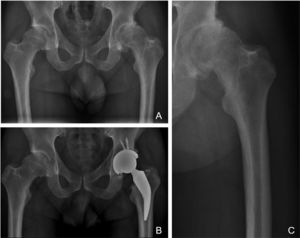

The philosophy of fixation of the stem researched classified as type 1B of the Kheir et al.,5 classification has a three-point fixation in the calcar area and proximal femoral cortex with metaphyseal fixation. The femoral neck and calcar resist the load and transfer it to the diaphysis. Preservation at the neck increases the rotational stability of the neck, which, together with metaphyseal fixation without diaphyseal invasion, avoids part of the incongruities seen in type A femurs of the Dorr classification which are more common in young adults.30 We believe this type of implant is a valid solution to potential femur-implant incompetence when placed in a Dorr A femur, since the short stem would not invade the canal at the diaphyseal level and would circumvent the conflict region, thus avoiding potential femoral fractures or problems in metaphyseal fixation of a standard, cementless stem when trying to insert it into a canal that is too thin. As can be seen in Fig. 3, where despite no preserving bone in the femoral neck, as suggested by the surgical technique and implant philosophy, the indication for implantation of a short stem would benefit from its potential revision with a metaphyseal–diaphyseal fixation stem, as it does not invade the diaphyseal region (Fig. 3).

X-rays of a 38-year-old male patient with diagnosis of advanced osteoarthritis of the left hip and who underwent THR. A) Preoperative AP X-ray where a lack of coverage of both hips is observed, with severe wear of his left hip and thick femoral cortices that could correspond to Dorr “A” classification. B) Immediate postoperative AP X-ray where a left THR is observed with restoration of his hip biomechanics; note the short stem does not invade the femoral canal at diaphyseal level, avoiding conflicts of femur-implant incompetence. C) X-ray focused on left preoperative hip where the potential conflict for implanting a cementless standard stem in a Dorr A femur is observed in greater detail.